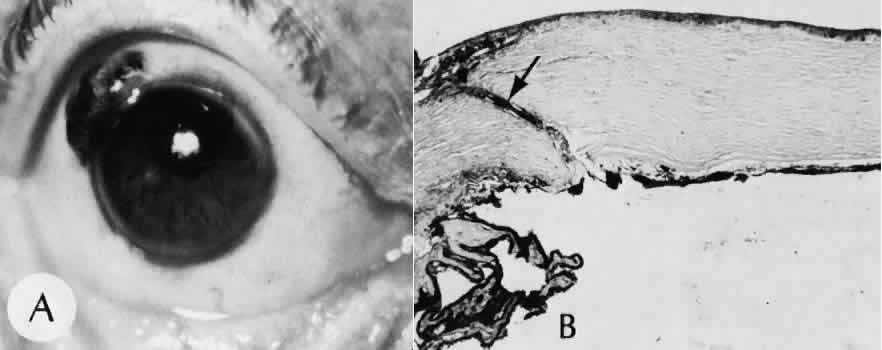

Granulation tissue often is the first type of reparative tissue in wound healing (Fig. 1). Although its composition varies somewhat, small-caliber vascular channels in a delicate collagenous stroma infiltrated by acute and chronic inflammatory cells generally characterize it. This amorphous tissue serves as a template for more definitive repair.

Fig. 1. Granulation tissue. A. Clinical photograph of granulation tissue (often mistakenly called a pyogenic granuloma) at the site of a ruptured chalazion. B. Granulation tissue growth in the region of a chalazion. The tissue has responded by forming multiple fine-caliber vascular channels associated with an infiltrate of acute and chronic inflammatory cells. The lightly stained areas in the tissue represent the response of fibroblasts and vascular endothelial cells to alter and augment the extracellular matrix. (Hematoxylin-eosin stain; × 100.)